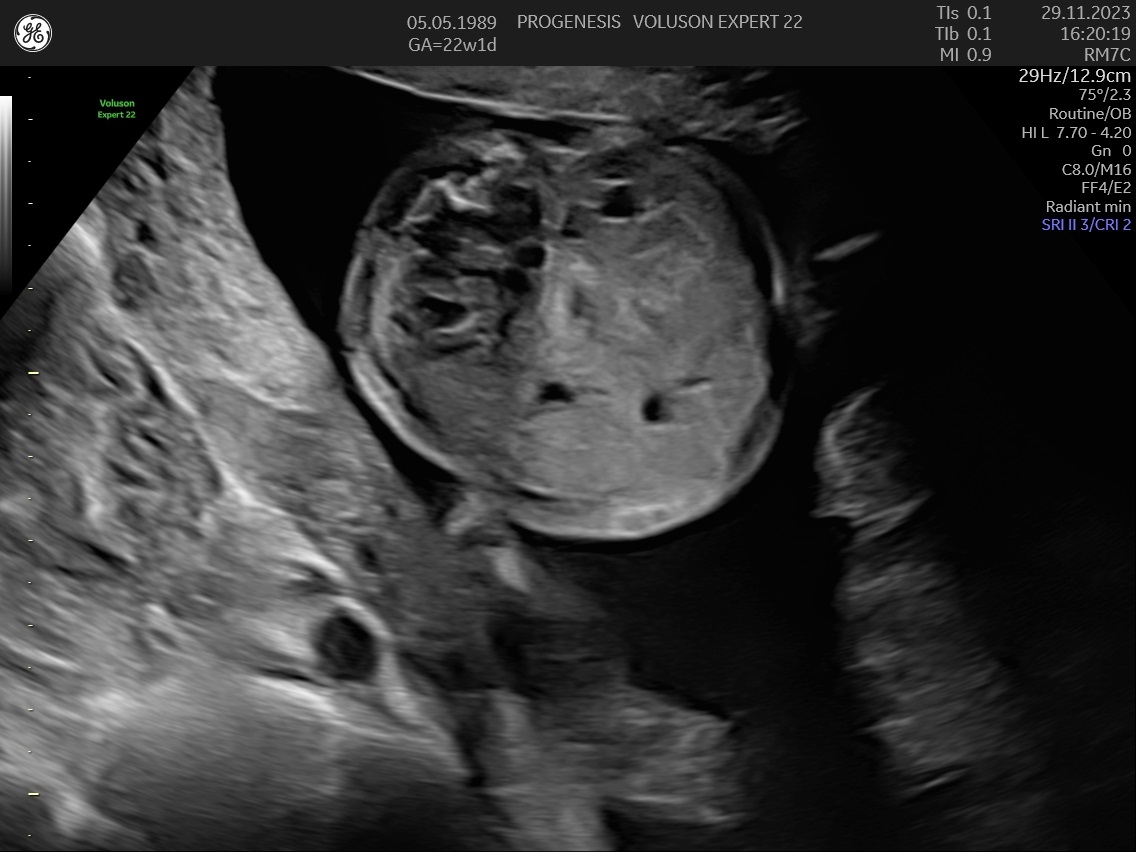

α) Η λεπτομερής αξιολόγηση της εμβρυϊκής ανατομίας, όπου αναγνωρίζονται τυχόν ανατομικές ανωμαλίες.

γ) Ο έλεγχος της ανάπτυξης του εμβρύου, του πλακούντα, του ομφαλίου λώρου και του αμνιακού υγρού.